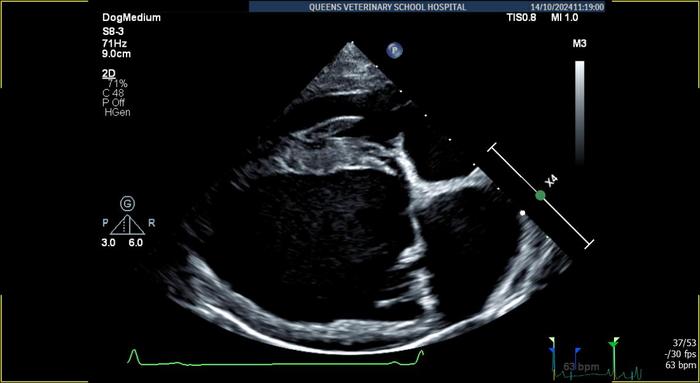

The researchers gathered data from almost 800 dogs who were undergoing routine heart examination at four veterinary specialist centres in the UK. All dogs received a full physical examination and heart scan (echocardiogram) by a cardiologist to grade any heart murmurs and identify cardiac disease, and heart sounds were recorded using an electronic stethoscope. By an order of magnitude, this is the largest dataset of dog heart sounds ever created.